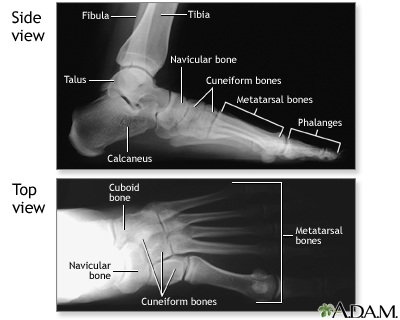

Normal foot x-ray

Along with questions of your medical history, your doctor may need to take x-rays of your foot to help aid in making a diagnosis to determine the cause of your foot pain. If the foot is broken it will be put into a cast. Toes that are broken are taped.